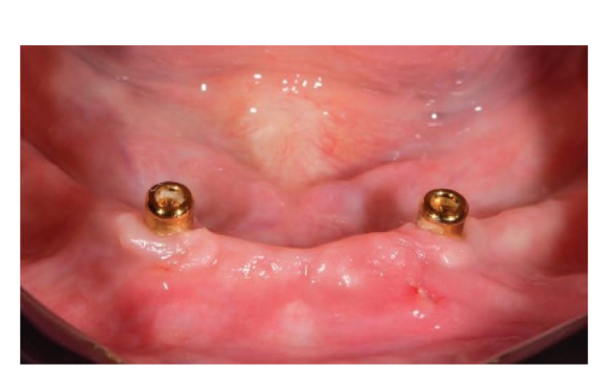

Dopo l'intervento, ai pazienti è stato consigliato di evitare qualsiasi trauma nel sito chirurgico, comprese le procedure di spazzolamento. È stata prescritta una dieta fredda e morbida post-chirurgica. Dopo l'intervento, ai fumatori è stato consigliato di astenersi dal fumo per due settimane. Sono state fornite istruzioni dettagliate per l'igiene orale, inclusa la raccomandazione di sciacquare tre volte al giorno con clorexidina allo 0,12%. Sono stati prescritti analgesici, come 600 mg di ibuprofene o alternative simili, secondo necessità. I punti di sutura sono stati tipicamente rimossi entro un periodo di dieci a quattordici giorni. Secondo un flusso di lavoro precedentemente riportato, le procedure protesiche sono iniziate otto settimane dopo l'inserimento degli impianti. Secondo un protocollo di carico precoce, una nuova dentiera rimovibile completa rinforzata in metallo è stata consegnata in entrambi i gruppi entro quattro settimane dopo l'inserimento degli impianti. Dopo due o tre giorni, gli abutment di guarigione sono stati svitati e gli attacchi sono stati collegati a lato della poltrona alla nuova protesi rimovibile. I pazienti sono stati randomizzati per ricevere attacchi OT Equator® (Rhein’83, Bologna, Italia) nel gruppo di test o attacchi Locator (Zest Anchors LLC) nel gruppo di controllo. I sistemi di attacco randomizzati sono stati posizionati e serrati secondo le istruzioni del produttore. Nel gruppo di test (Figure 1–5), dopo la guarigione gengivale, i più recenti attacchi OT Equator® a basso profilo sono stati avvitati sugli impianti utilizzando il cacciavite quadrato OT Equator®, con un intervallo di coppia di 22–25 Ncm. Le altezze dei manicotti variavano da 0,5 a 7,0 mm, a seconda delle dimensioni della zona di transizione di ciascun impianto, facilmente misurabili utilizzando il misuratore di altezza del manicotto millimetrico a codifica colore (Rhein’83, Bologna, Italia) dopo la rimozione dell'abutment di guarigione. Successivamente, è stato preparato lo spazio necessario per accettare la gabbia in acciaio della sede femminile nella superficie di adattamento della dentiera rimovibile completa mandibolare. Dischi protettivi in silicone (Rhein’83, Bologna, Italia) sono stati posizionati sopra gli attacchi OT Equator®. Cappucci di ritenzione extra-morbidi (giallo, 600 g) sono stati inizialmente inseriti nella sede femminile in acciaio, attaccati a OT Equator®, e infine fissati alla dentiera utilizzando resina acrilica autoindurente. Allo stesso tempo, il paziente ha tenuto le dentiere in occlusione, direttamente a lato della poltrona. Dopo la completa polimerizzazione, la dentiera è stata prelevata e i dischi in silicone sono stati rimossi. L'eccesso di acrilico è stato rifilato e la dentiera è stata rifinita e lucidata. Un mese dopo la consegna delle protesi, i cappucci di ritenzione gialli sono stati sostituiti con un tipo più robusto (rosa, 1200 g).

Nel gruppo di controllo (Figure 6–10), l'attacco Locator (Zest Anchors LLC) è stato avvitato sugli impianti utilizzando il cacciavite Locator (Zest Anchors LLC), con un intervallo di coppia di 20–25 Ncm. Le altezze delle maniche di 2,5 o 4,0 mm, a seconda della dimensione della zona di transizione di ciascun impianto, sono state misurate utilizzando la sonda profonda della linea di impianti dopo la rimozione dell'abutment di guarigione. Successivamente, sono stati preparati spazi per accettare la gabbia in acciaio della custodia femminile sulla superficie di adattamento della protesi totale rimovibile mandibolare. Anelli bianchi protettivi in silicone (Zest Anchors LLC) sono stati posizionati sopra gli attacchi Locator. Cappucci neri passivi sono stati utilizzati per caricare l'attacco, attaccato al Locator, e infine fissato alla protesi utilizzando resina acrilica autoindurente, mentre il paziente teneva le protesi in occlusione, direttamente a fianco della poltrona. Dopo la completa polimerizzazione, la protesi è stata prelevata e gli anelli bianchi sono stati rimossi. L'eccesso di acrilico è stato rifilato e la protesi è stata rifinita e lucidata. I cappucci neri sono stati rimossi e quelli blu (6N) sono stati montati nella custodia in acciaio. Un mese dopo la consegna delle protesi, i cappucci di ritenzione sono stati sostituiti con una matrice rosa (12N).